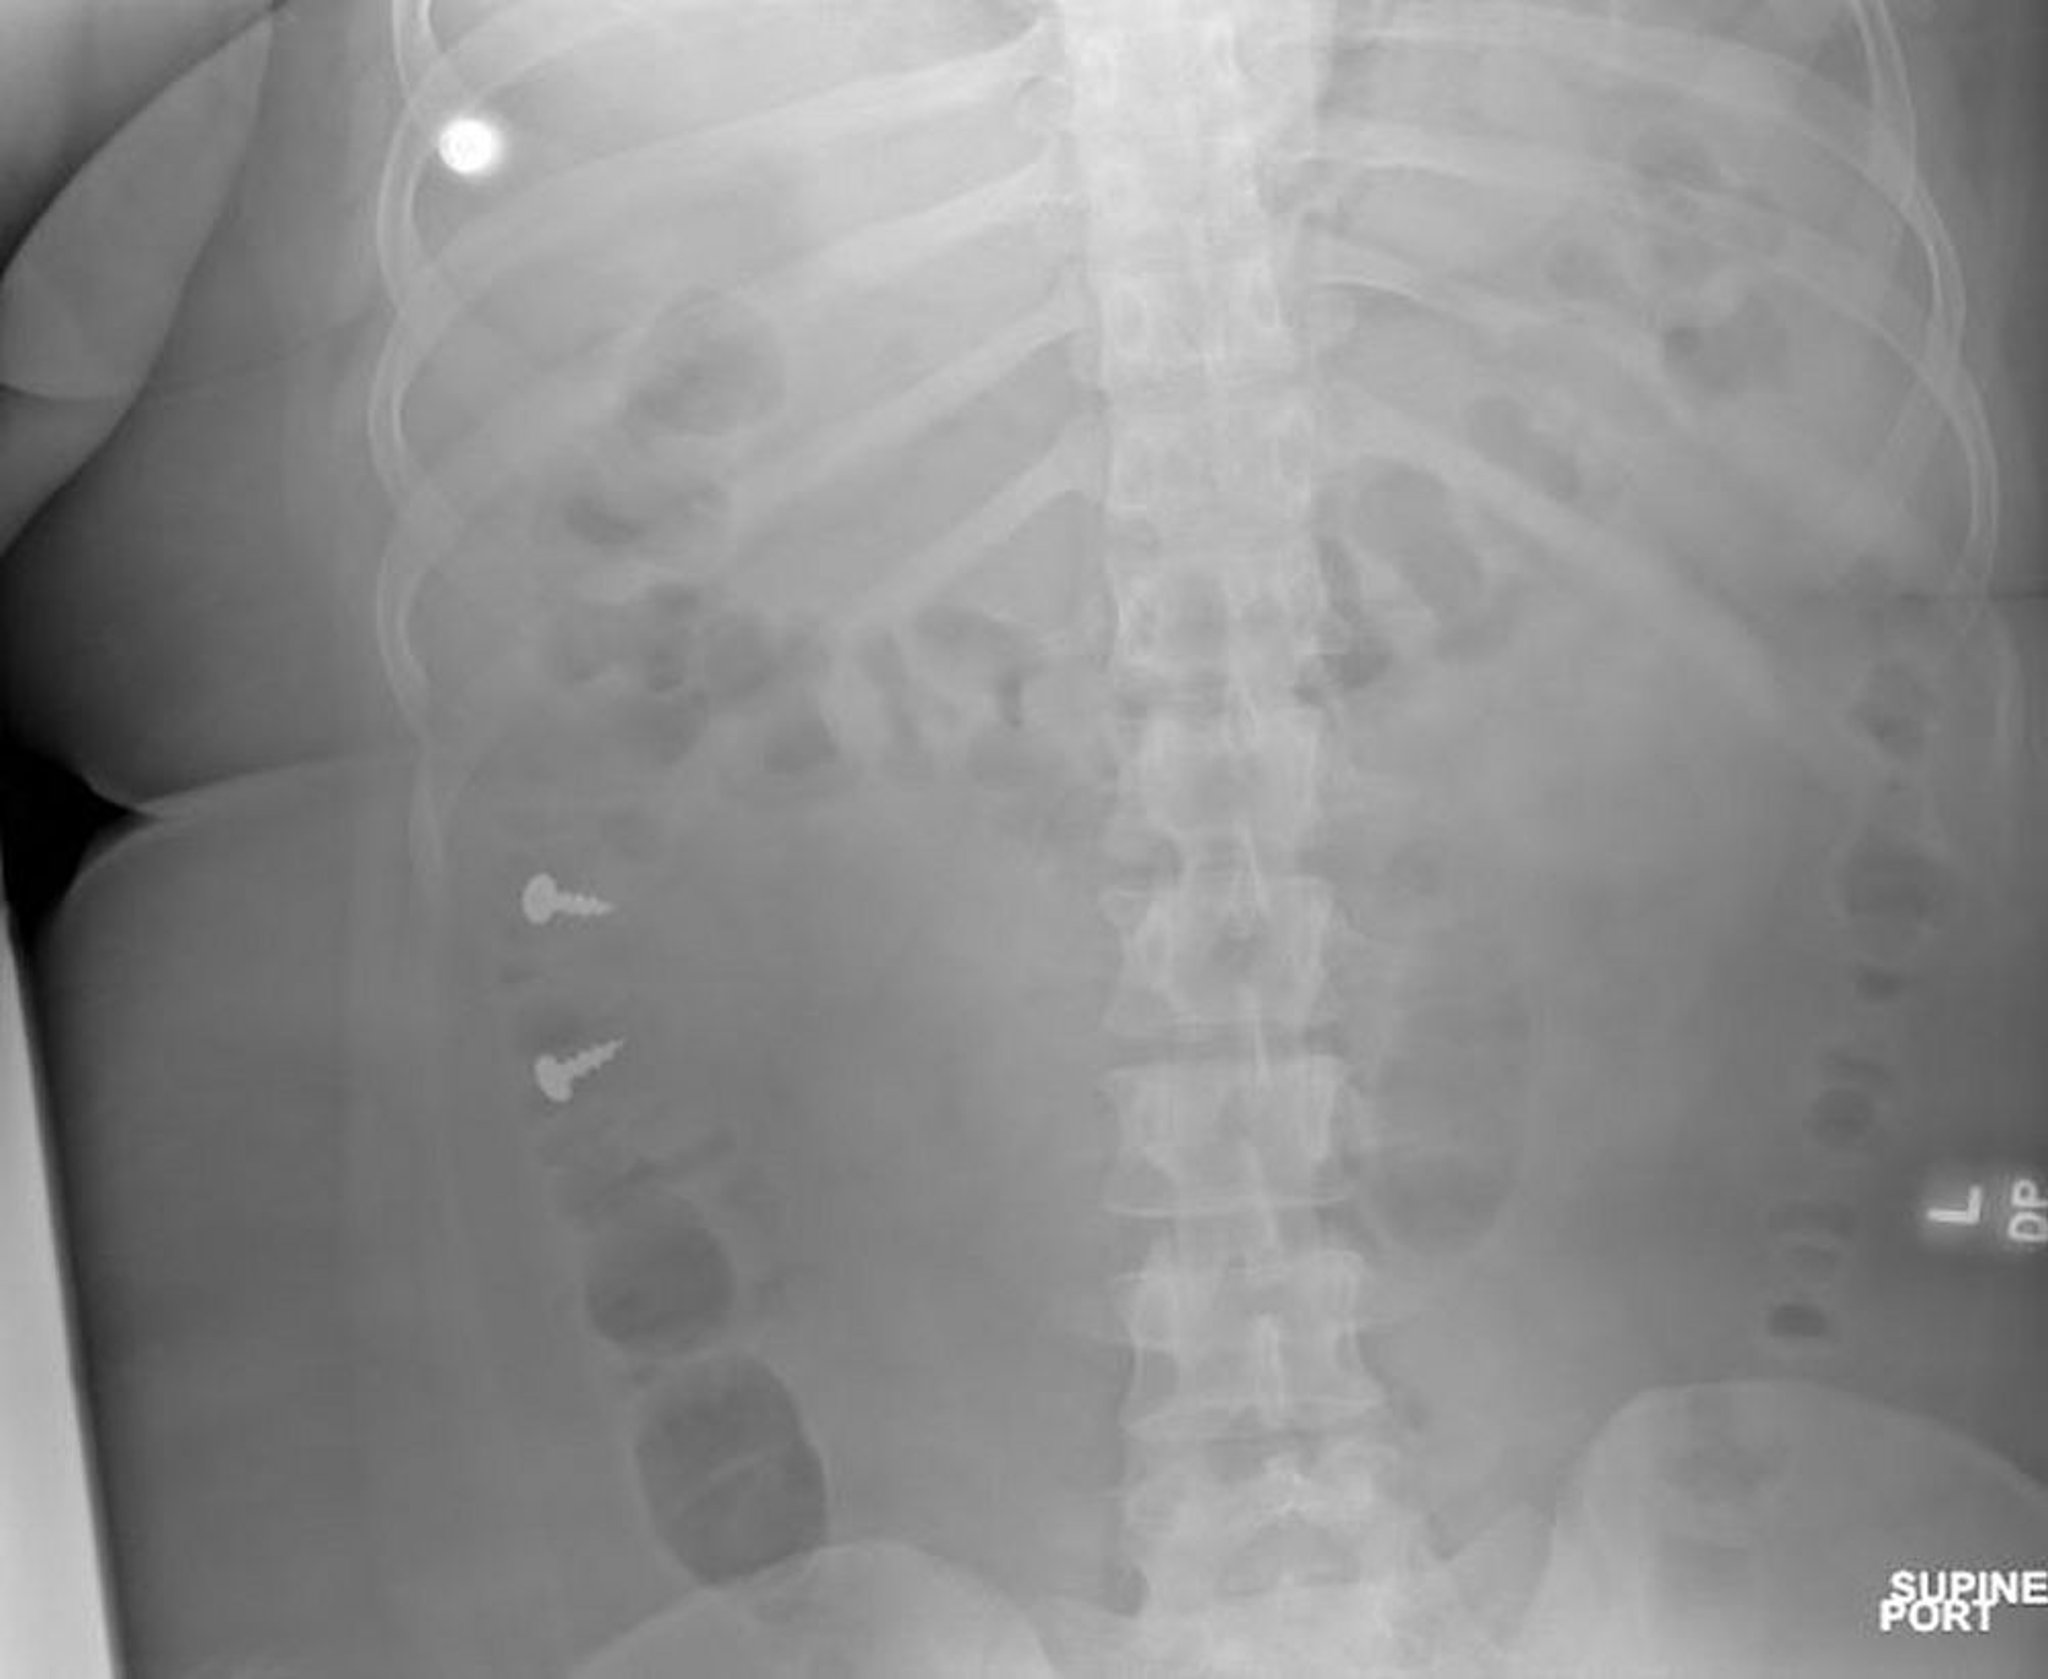

Винты в толстой кишке (рентгенография)

Image courtesy of Zubair Malik, MD.

Инородные тела в желудке и кишечнике